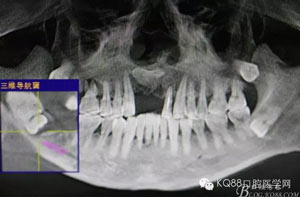

圖1。術(shù)前檢查的口內(nèi)像:48區(qū)域的位置有一瘺口。捫診溢膿。48未萌出。